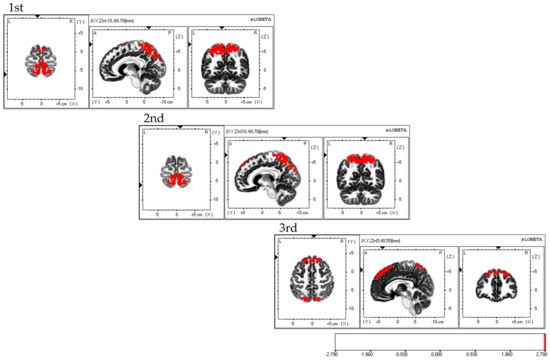

Considering the areas of cerebral neural activity during BCAS, the first session demonstrated predominant neural activity in the bilateral supplementary motor cortex and inferior parietal lobule, mainly in the bilateral superior parietal lobule. The second session demonstrated predominant neural activity in the supplementary motor cortex and superior parietal lobule, primarily in the bilateral dorsolateral prefrontal cortex. The third session demonstrated predominant neural activity in the bilateral supplementary motor cortex, with predominant neural activity in the dorsolateral premotor cortex, dorsolateral prefrontal cortex, and superior parietal lobules (Figure 6). Each of the three sessions exhibited fluctuations in the areas of brain activity.

Figure 6.

Neural activity during BCAS. The results of the EEG using eLORETA upon using the BCAS are as follows: the first session exhibited predominant neural activity mainly in the bilateral superior parietal lobes but also in the bilateral supplementary motor cortex and inferior parietal lobule; the second session demonstrated predominant neural activity mainly in the bilateral dorsolateral prefrontal cortex, along with the supplementary motor cortex and superior parietal lobule; the third session exhibited predominant neural activity in the bilateral supplementary motor cortex, along with the dorsolateral premotor cortex, dorsolateral prefrontal cortex, and superior parietal lobule. Variations in brain activity were observed after each session. The eLORETA scale depicts the brain regions with activity values above two standard deviations of the neural activity value (µV/mm2) in red. BCAS: body cognition assessment system; eLORETA: exact low-resolution brain electromagnetic tomography.